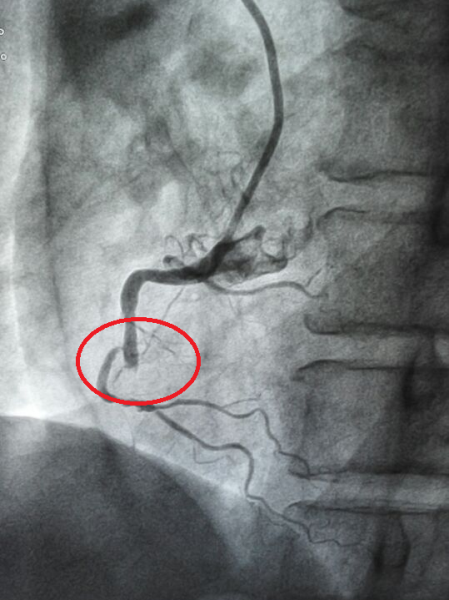

治疗前

由于患者对疾病缺乏认知,在家耽误时间较长,入院后与家人沟通又花费了近一个小时,影响了手术效果。对于急性心肌梗死的患者来说,时间就是生命,血管开通时间越早,挽救的心肌越多。所以积极的治疗措施是起病12小时内使闭塞的冠状动脉再通,心肌得到再灌注,濒临坏死的心肌可能得以存活或坏死范围缩小,对梗死心肌重塑有利,改善预后。